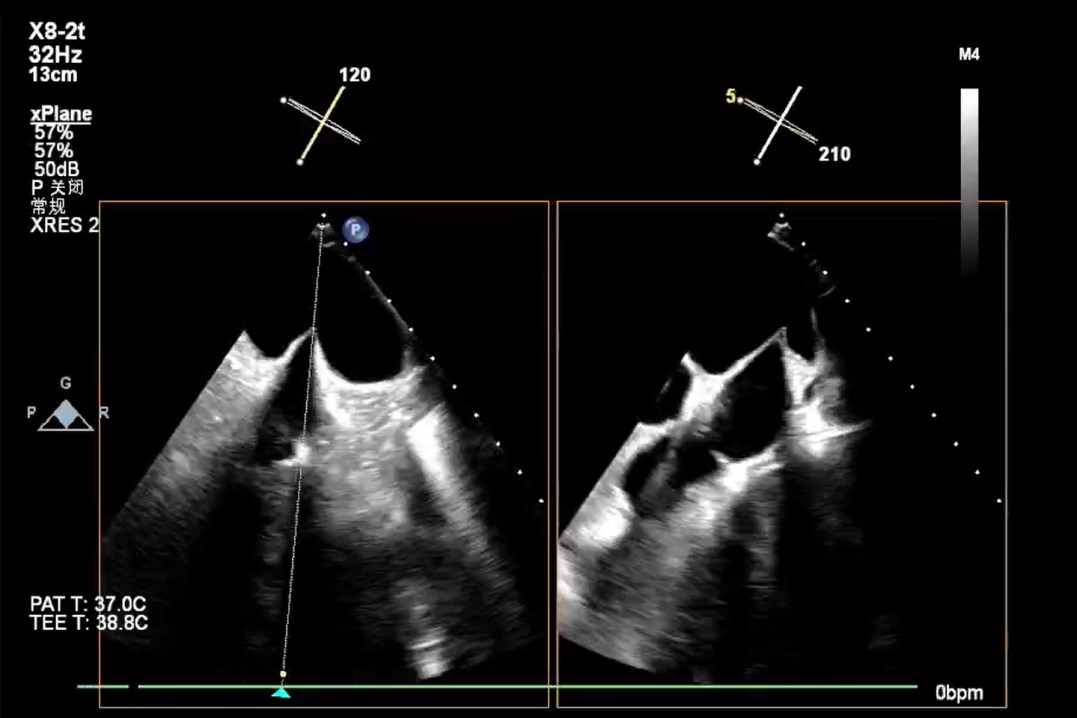

术前X-plane

术前X-plane Color

术前X-plane

术前X-plane Color

术前X-plane

术前超声 Color

术前X-plane

术前X-plane Color